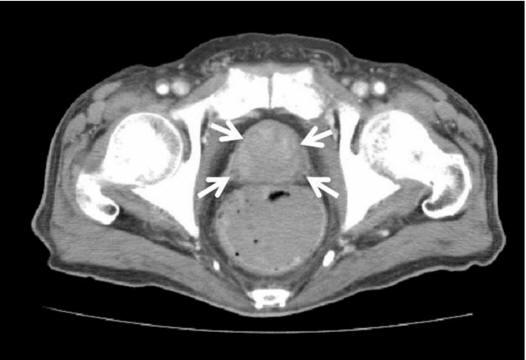

This is one measure of prostate cancer risk, since psa levels can rise rapidly in men who have prostate cancer. Prostate Cancer Testing & Surgical Options - By Peter J